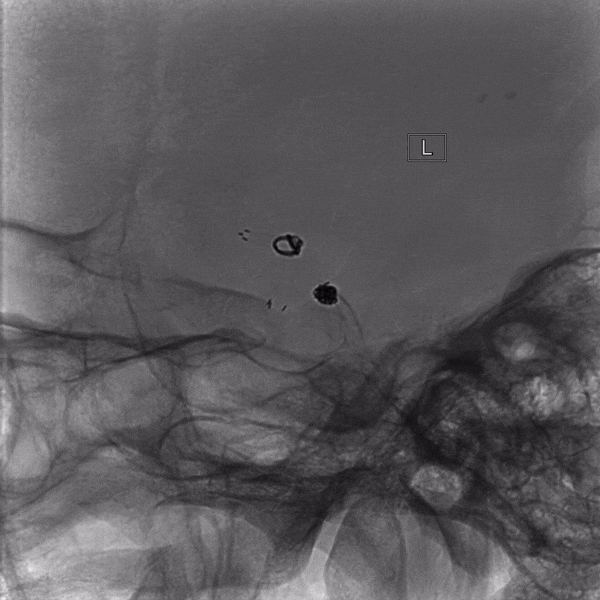

左侧颈内动脉造影

1.左侧大脑前动脉A1起始部未破裂动脉瘤(囊性)

2.右侧大脑前动脉A1起始部未破裂动脉瘤(夹层)